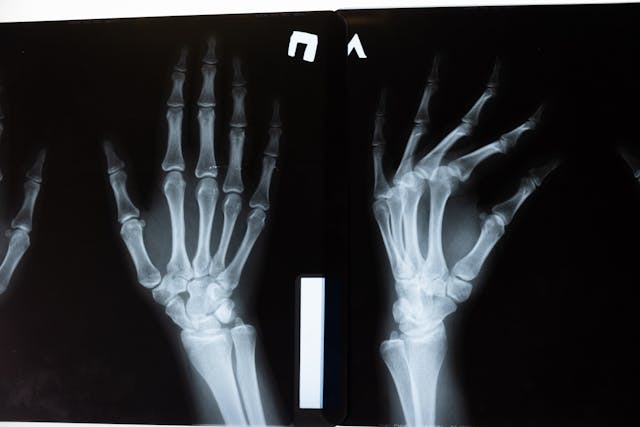

특별히 아프지도 않았고, 전조 증상도 없었는데 어느 날 갑자기 골절로 병원을 찾게 되는 경우가 있습니다. 바로 골다공증 때문입니다. 골다공증은 겉으로 드러나는 증상이 거의 없어 ‘침묵의 질환’이라 불리지만, 한 번 골절이 발생하면 생명과 삶의 질에 큰 영향을 줄 수 있어 각별한 주의가 필요합니다.

- 가벼운 낙상 후 손목·엉덩이 골절

- 키가 줄거나 등이 굽는 척추 압박골절

특히 고령자의 대퇴골 골절은 회복이 느리고 장기간 침상 생활로 이어져 수술 후 합병증과 사망 위험이 높아질 수 있습니다.